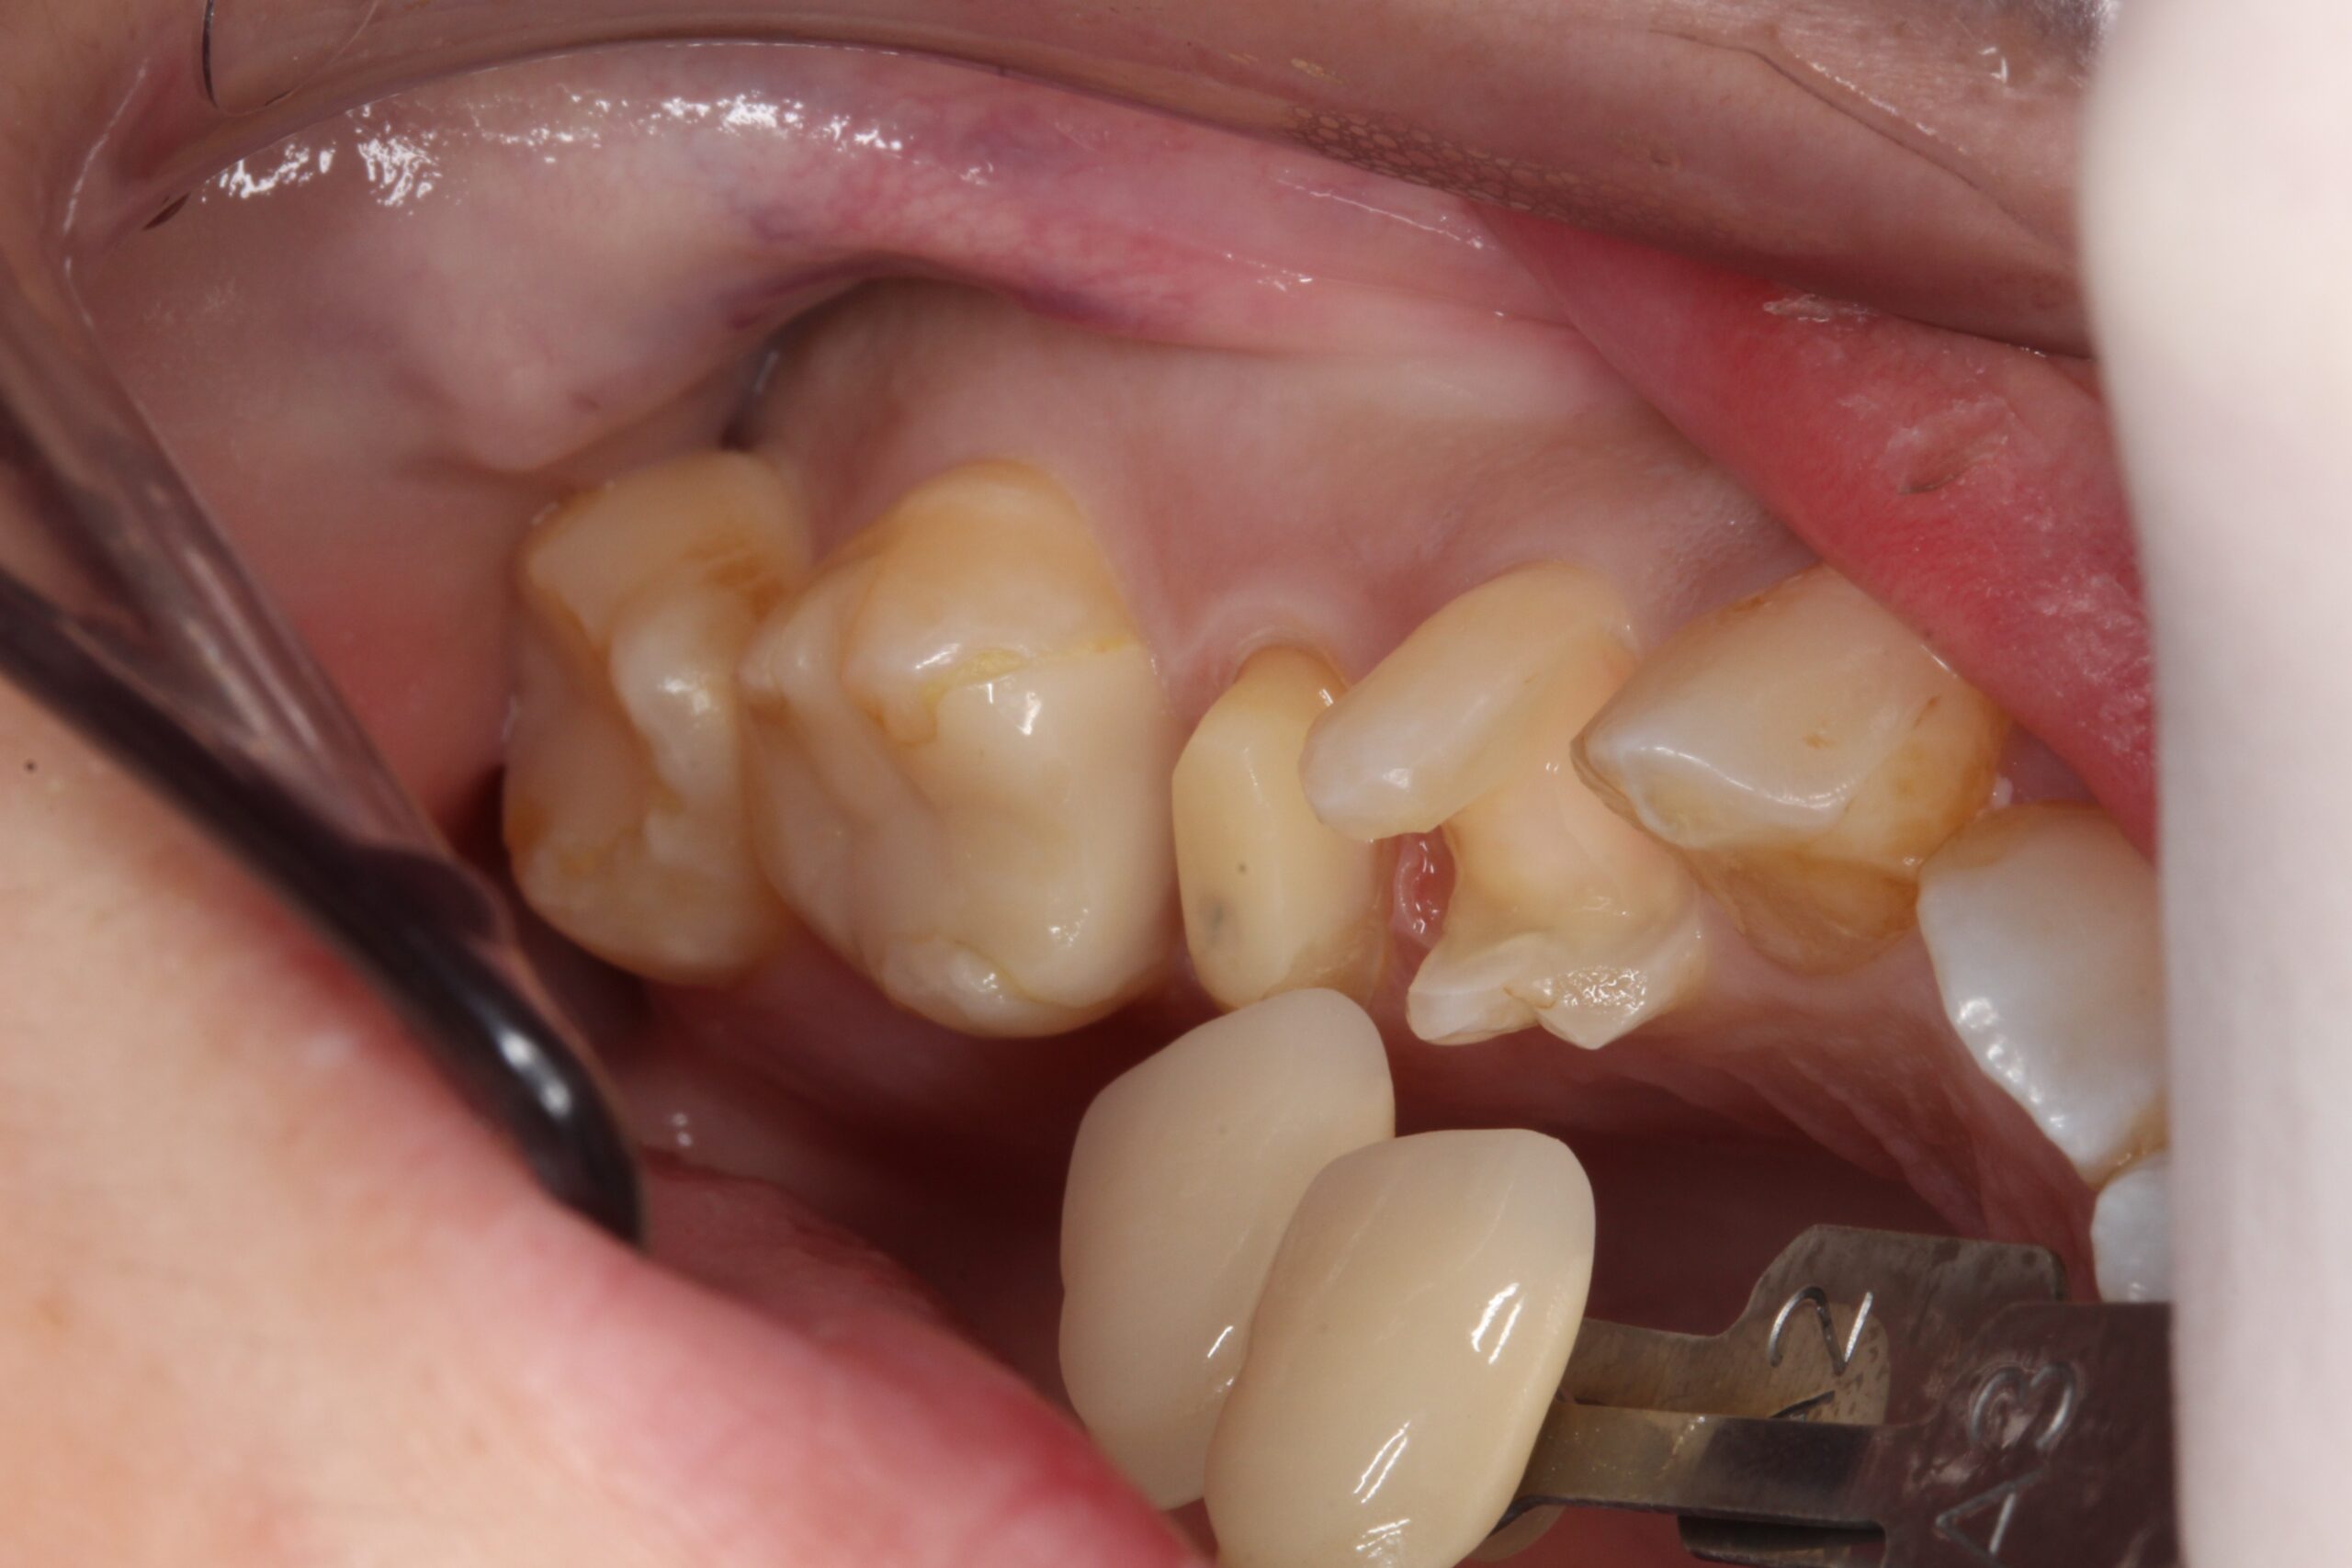

30代女性 根管治療と虫歯治療を。その②

• Before

After

30代女性 根管治療と虫歯治療を。その①